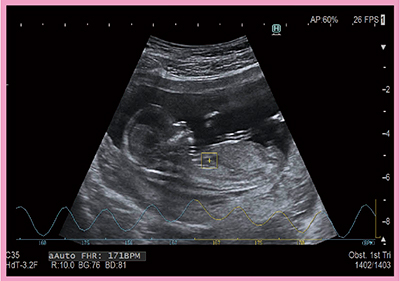

2.自動胎児心拍数計測機能“AutoFHR”

胎児心拍数(fetal heart rate:FHR)の計測は,従来,ドプラ法もしくはMモード法で行われてきたが,胎芽の段階では安全性の観点からドプラ法は推奨できず,また,Mモード法では胎動や母体の呼吸などの影響により計測困難である。そこで,胎児心拍数を自動で計測するAutoFHR(図6)が開発された。

AutoFHRは,超音波断層上の画像情報(スペックル)を基に組織を追跡する断層組織トラッキング(2D tissue tracking:2DTT)法を応用した手法である。パターンマッチング法を用いてBモード画像上の特徴量の変移を自動で経時的かつ正確に計測できるため,将来的にはMモード法に取って代わる可能性がある。現状では,リアルタイムでの計測はできないが,安全性が高く,簡便であることから,臨床に役立つと期待している。

図6 AutoFHRによる胎児心拍数の計測